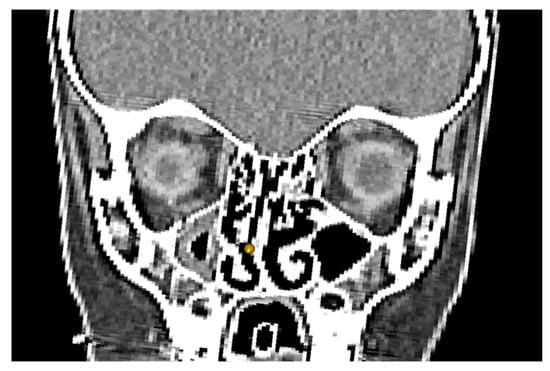

Figure 2. Coronal slice of a male specimen showing a landmark placed on the most laterally deviated point of the nasal septum. Image created using Avizo 9.0 (FEI visualisation). Interslice distance 0.5 mm.

2.2. Landmark Configuration